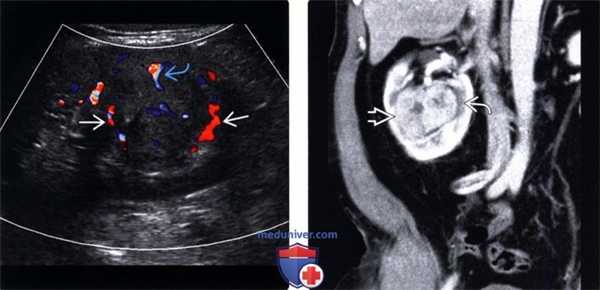

(Левый) На продольном УЗ срезе с цветовой допплерографией у пациента со светлоклеточным ПКР визуализируется выраженная внутренняя и периферическая васкуляризация в солидной опухоли.

(Правый) На фронтальном КТ срезе с контрастированием у этого же пациента визуализируется многокамерный, накапливающий контраст ПКР с четкими контурами. Обратите внимание на гиподенсивный ободок.